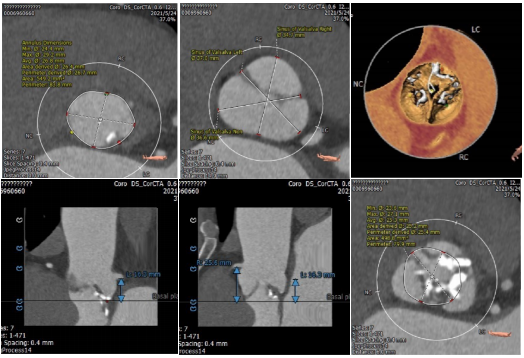

根部评估

Type1型二叶式主动脉瓣,L-N融合,主动脉瓣环周长83.8mm,平均周长径26.8mm。瓦式窦可。左冠开口高度16.3mm,右冠开口高度25.6mm。